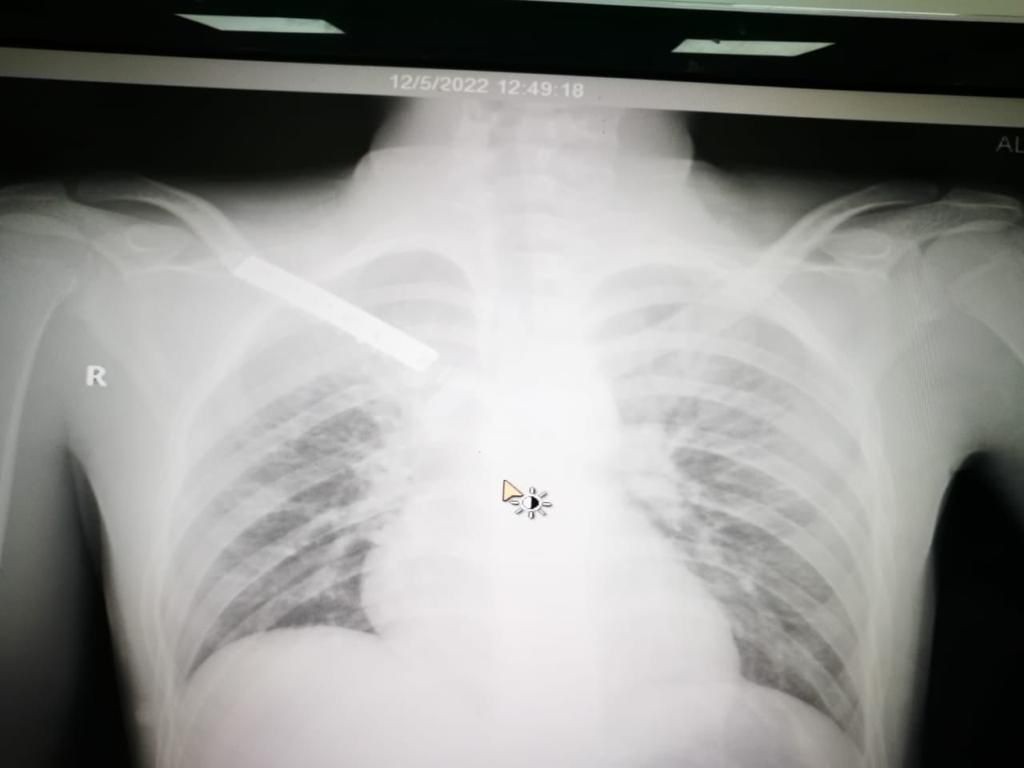

تمكن فريق طبي في منطقة تبوك من إجراء عملية دقيقة ومعقدة لإرجاع عظم الترقوة والقفص الصدري إلى مريض تعرض لحادث مروري إستغرقت مدتها 4 ساعات تكللت ولله الحمد بالنجاح. وقالت صحة تبوك إن أطباء مستشفى الملك خالد في منطقة تبوك تمكنوا ولله الحمد من إنقاذ حياة شاب وصل لقسم الإسعاف بحالة حرجة نتيجة تعرضه لحادث مروري فقد بسببه كميات كبيرة من الدم جراء النزيف الذي فقده الجسم ، وتم تقديم الإسعافات الطبية الأولية العاجلة لإيقاف النزيف. وأكدت أنه بعد إجراء الفحوصات السريرية والإشعاعية والمخبرية تبين وجود انفصال تام لعظم الترقوة مع عظم القفص الصدري بالإضافة إلى كدمات في الرئة وكسور في عظام الحوض وخلع في المفصل مما استدعى دخوله بشكل عاجل لغرفة العمليات الكبرى وإجراء عملية أمامية على الصدر شملت المفصل القصي الترقوي وعظم الترقوة اليمنى مترادفات وإزالة الضغط على القسم العلوي من الرئة والشريان والأوردة والأعصاب التي تغذي الطرف العلوي وتفريغ التجمع الدموي الناتج عن الخلع والكسر وإعادة الجزء المكسور من الترقوة من داخل القصي والربط بين الضلع الأيمن الأول والترقوة للمحافظة على ثبات المفصل، حتى استقرت الحالة لتنقل بعدها إلى غرف التنويم لاستكمال المتابعة الطبية لها حتى الخروج من المستشفى- بإذن الله- بصحة جيدة. يذكر أن مستشفى الملك خالد خلال ال (3) الأشهر الماضية أجرى أكثر من 1031 عملية منها 381 عملية طارئة و 650 عملية روتينية.